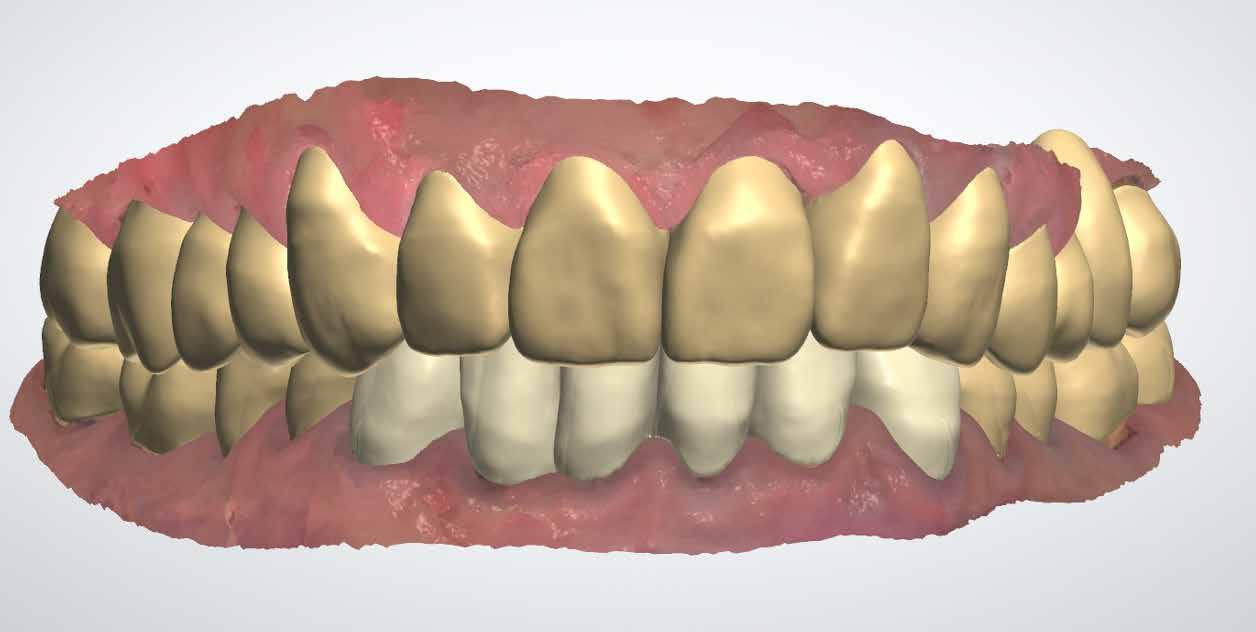

Ebben a cikkben egy olyan esetet ismertetünk, ahol a kezelés során alkalmazott munkafolyamatokat digitálisan végeztük el. Minimál-invazív preparációt követően – digitális mosolytervezés alapján – lithium-diszilikát tömbökből monolitikus héjakat és koronákat készítettünk CAD/CAM technológia felhasználásának segítségével. Az elkészült restaurátumok segítségével helyreállítottuk az elvesztett harapási magasságot, valamint megszüntettük az ebből adódó esztétikai hátrányokat és az emiatt kialakult temporomandibuláris ízületi diszfunkciót.

Esetbemutatás

2015-ben egy 47 éves férfi páciens állkapocs-ízületi panaszai miatt kereste fel a rendelőnket. Ezen felül esztétikai problémát jelentett számára, hogy az egyik felső nagymetszőfogán lévő héj eltört (1-3. ábrák). A klinikai és radiológiai vizsgálatot követően megállapítható volt, hogy a páciens kifejezett bruxizmusa miatt csökkent a harapási magassága, és jelentős mennyiségű saját foganyagot abradált el (4. ábra)

A páciens a megkezdett kezelések folytatása miatt 2017ben ismét felkereste a rendelőnket (7. ábra). Ekkor egy új intraorális lenyomatvétel történt (Carestream 3600).

A fogak preparálásához egy új mock-upot készítettünk háromdimenziós nyomtató segítségével (SolFlex, VOCO) bisz-akrilátból (Structur 3). A mock-up elkészítéséhez felhasznált sablont vákuum technológia segítségével hoztuk létre (V-Print ortho, VOCO). A mock-up felhelyezését követően a páciens fogait minimál invazív módon készítettük elő (8. ábra).

A már előzetesen preparált felső frontfogak csiszolt csonkjainak megtartottuk az eredeti formáját. Az alsó és felső őrlőfogak preparációja nem volt szükséges (1.7-1.4, 2.4-2.7, 3.7-3.4, 4.4-4.7), az alsó kismetsző fogakat minimál invazív módon készítettük elő. Az előkészítést követően új digitális lenyomat készült. Az így kapott digitális adatokat továbbítottuk a fogtechnikai laboratóriumba (9. ábra). A virtuális modellt ezek alapján hozták létre (AnatomicLab), és a minta elkészítéséhez szükséges STL fájlt továbbították egy háromdimenziós nyomtatóra (SolFlex 650, VOCO), amely segítségével elkészítették az új mintát (V-Print model, VOCO).

A végső restaurátumokat (héjakat és koronákat) Ce-

ramill Mind tervező program segítségével (AmannGirrbach) digitálisan megtervezték, majd frézgép segítségével (CeramillMotion 2, AmannGirrbach) li thium-diszilikát tömbökből (VITABLOCS TriLuxe forte for CeramillMotion 2, AmannGirrbach) kifaragták (10. ábra). Miután a fogpróba során ellenőrizték és megfelelőnek találták a pótlások széli záródásának a pontosságát, valamint az elkészült restaurátumok esztétikai megjelenését, ezután egy ajak- és szájterpesz került felhelyezésre (OptraGate, IvoclarVivadent).

A koronákat (1.3-1.1 és 2.1-2.3) és a héjakat (1.7-1.4, 2.4–2.7, 3.7-3.1, 4.1–4.7) fényrekötő adhezív rendszerrel rögzítették a pillérfogakhoz (Futurabond U ésBifix QM, VOCO). A polimerizációhoz egy nagy teljesítményű LED polimerizációs lámpát használtak (Celalux 3, VOCO), (1112. ábrák).

A kifolyó ragasztóanyagot ezt követően eltávolították, majd az okklúziót a T-Scantechnológia (Tekscan) segítségével ellenőrizték, majd a szükséges mértékben korrigálták. A véglegesen rögzített kerámiapótlás védelme érdekében a páciensnek a továbbiakban egy kivehető, átlátszó műanyag fogvédő sínt kellett viselnie. A pótlásokat 6 hónap múlva ellenőrizték. Az át adott fogpótlások stabilan rögzültek, és nem találtunk sérülésekre, repedésekre utaló jeleket (13-15. ábrák). A páciens arról is beszámolt, hogy a harapás megemelése óta megszűntek az őt rendszeresen gyötrő fejfájásai.